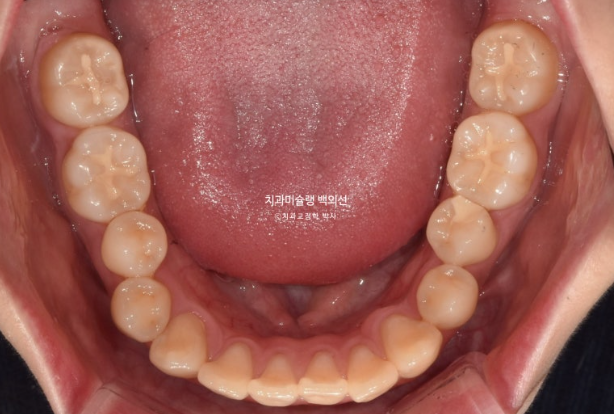

교합은 거꾸로 물리는 어금니 반대교합도 있고, 뜨는 부분도 있고 앞니 하나는 신경치료 후 변색이 되어 있습니다.

어금니 교합은 좋습니다.

배열도 대부분 완료되었습니다.

위 앞니 기준 약 2mm 합입이 되었습니다.

위 어금니도 마찬가지로 약 2mm 합입이 되었습니다.

한마디로 상악 전체치열이 2mm 합입되었고 뒤로는 약 2mm 후방이동 하였습니다.

앞니뿐 아니라 어금니까지 상악 14개 전체치열의 후방이동 및 합입으로 아래턱이 자가회전하며 턱끝이 짧아졌습니다.